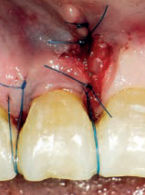

Zastosowanie fibryny bogatopłytkowej w zabezpieczaniu zębodołów poekstrakcyjnych – aktualny przegląd piśmiennictwa i doświadczenia własne

Use of platelet rich fibrin (PRF) in socket preservation – current literature review and own experiences

Marta Malujda, Joanna Gołowkin, Agnieszka Droździk